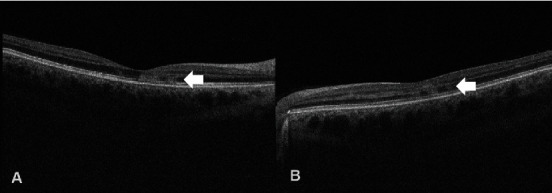

据我们所知,这是我们发现的首例Ⅱ型急性黄斑神经视网膜病变(AMN)病例,患者患有疟原虫性视网膜病变,同时伴有脑疟疾,在前往西非旅行时未采取必要的抗疟预防措施。患者在重症监护室解除镇静后,主诉双侧视力模糊。随后的检查发现双侧视网膜出血、棉絮状斑点和眼窝色素改变,表明患者患有疟原虫视网膜病变。黄斑光学相干断层扫描(OCT)显示,丛状外层和核外层(ONL)出现斑片状高反射变化,与 OCT 血管造影(OCT-A)显示的深层毛细血管丛流动空洞区域一致。本病例报告进一步揭示了疟原虫视网膜病变中神经感觉视网膜缺血的程度,并展示了一种新的成像生物标志物,可用于评估和量化该疾病造成的功能障碍。

To the best of our knowledge, we present the first case of type II acute macular neuroretinopathy (AMN) exhibiting in a patient suffering from malarial retinopathy concomitant with cerebral malaria acquired after travelling to West Africa without taking the necessary antimalarial prophylaxis. The patient complained of bilateral blurring of vision after being removed off sedation whilst at the intensive care unit. Subsequent examination revealed bilateral retinal haemorrhages, cotton-wool spots, and foveal pigmentary changes in keeping malarial retinopathy. Macular optical coherence tomography (OCT) revealed patchy hyperreflective changes at the level of the outer plexiform and outer nuclear layers (ONL) in keeping with the areas of deep capillary plexus flow void noted on OCT-angiography (OCT-A). This case report sheds more light on the extent of neurosensory retinal ischaemia in malarial retinopathy and showcases a new imaging biomarker which may be utilized in assessing and quantifying the functional deficit created by this disease.